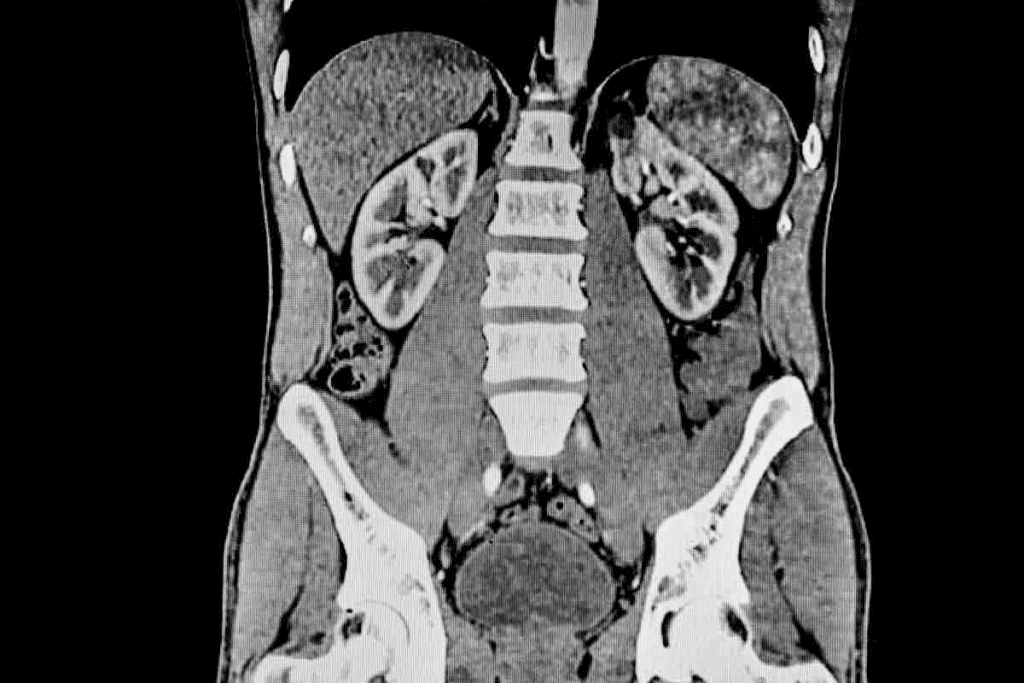

Renal CT scans are key in spotting many kidney issues. CT scans of the kidneys give detailed pictures. These help doctors diagnose and treat kidney diseases.

What Kidney CT Scans Can Detect

Kidney CT scans find many problems, like renal stones, tumors, infections, and cysts. They’re great for spotting kidney stones. These can cause a lot of pain and serious issues if not treated right away.

CT scans help doctors plan the best treatment. For example, they can show how big and where kidney stones are. This helps decide if surgery is needed.

Common Conditions Diagnosed with Renal Imaging

Renal imaging with CT scans is key in finding many kidney issues. Some common ones include:

- Kidney Disease: CT scans spot problems like cysts or tumors in kidney disease.

- Renal Cell Carcinoma: A kidney cancer type that CT scans can find.

- Pyelonephritis: A kidney infection that CT scans can diagnose.

Knowing how renal CT scans work helps patients understand their health better. With the detailed images from CT scans, doctors can give more precise and effective care.